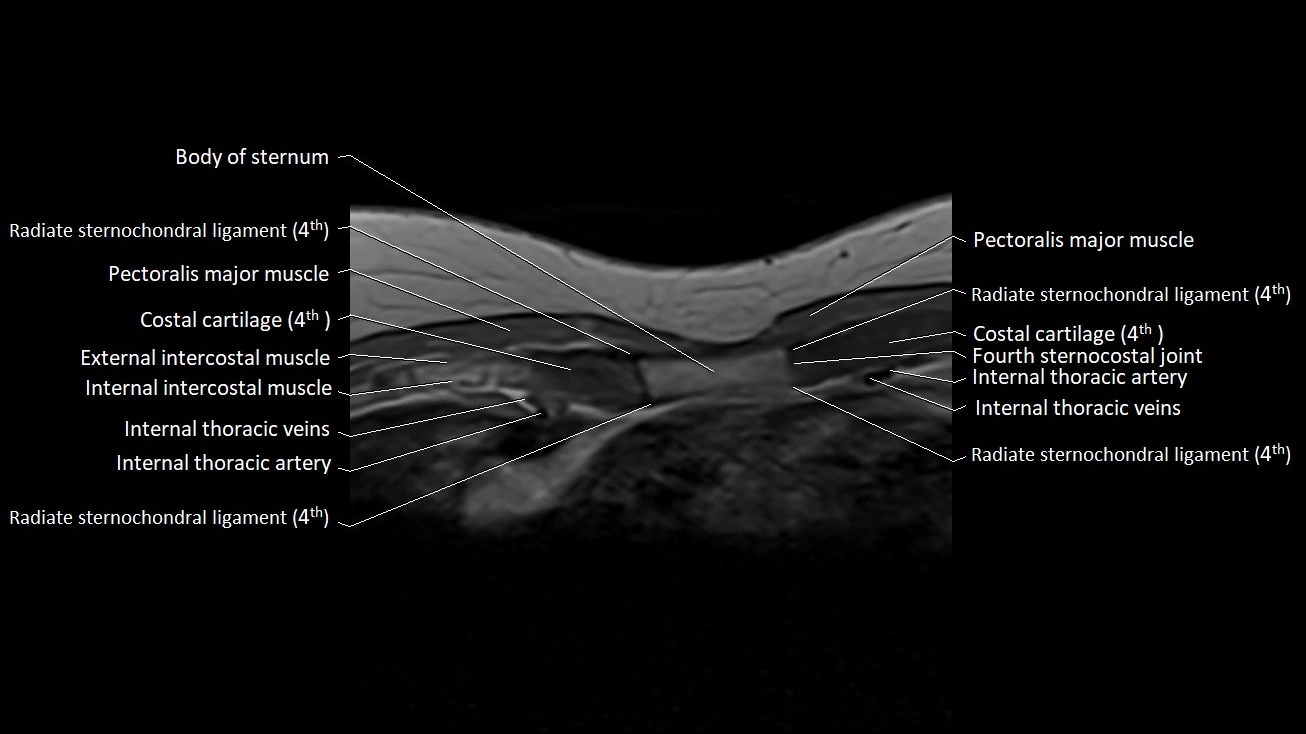

MRI images

image